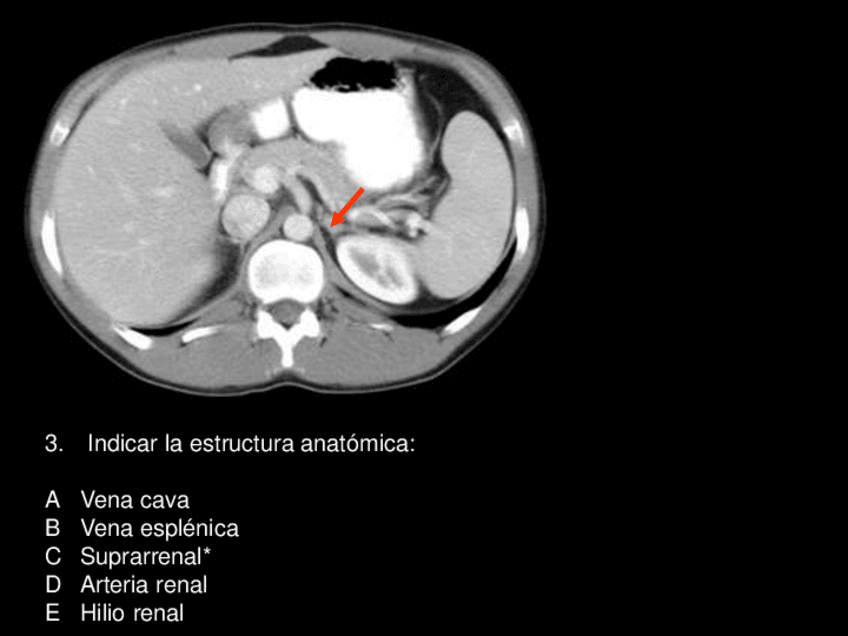

Exámenes - examen-practico-2.pdf

24 páginas